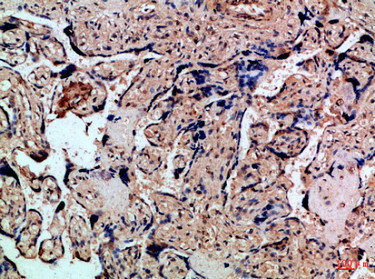

Immunohistochemical analysis of paraffin-embedded Human-liver-cancer, antibody was diluted at 1:100